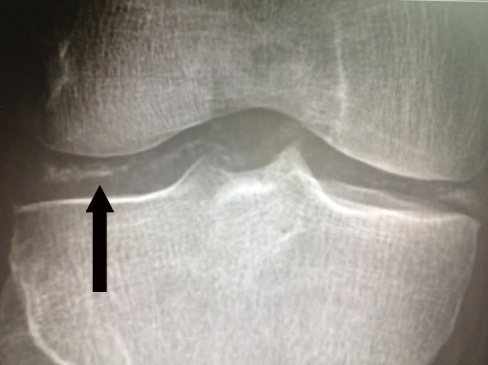

Giant Cell Tumor

This patient's x-ray findings of an expansile and eccentric lytic area ("soap-bubble" appearance) are highly suggestive of giant cell tumor of bone (GCTB). GCTB is a benign and locally aggressive skeletal neoplasm seen in young adults. Patients usually present with pain, swelling, and decreased range of joint motion at the involved site. Nearly 10%-35% of affected patients experience pathologic fractures due to thinning of the bone cortex in weight-bearing areas.

GCTB typically presents on x-ray of the epiphyseal regions of the long bones, most commonly the distal femur and proximal tibia around the knee joint. Magnetic resonance imaging can show the tumor containing both cystic and hemorrhagic regions. Pathology typically shows sheets of interspersed large osteoclast giant cells that appear as round-to-oval polygonal or elongated mononuclear cells. Surgery (eg, intralesional curettage with or without bone grafting) is first-line treatment for GCTB.

X-ray of the knee typically shows avulsion of the apophysis of the tibial tubercle.

Knee x-ray findings in patients with osteoarthritis include joint space narrowing, subchondral sclerosis, osteophyte formation, and subchondral cysts.